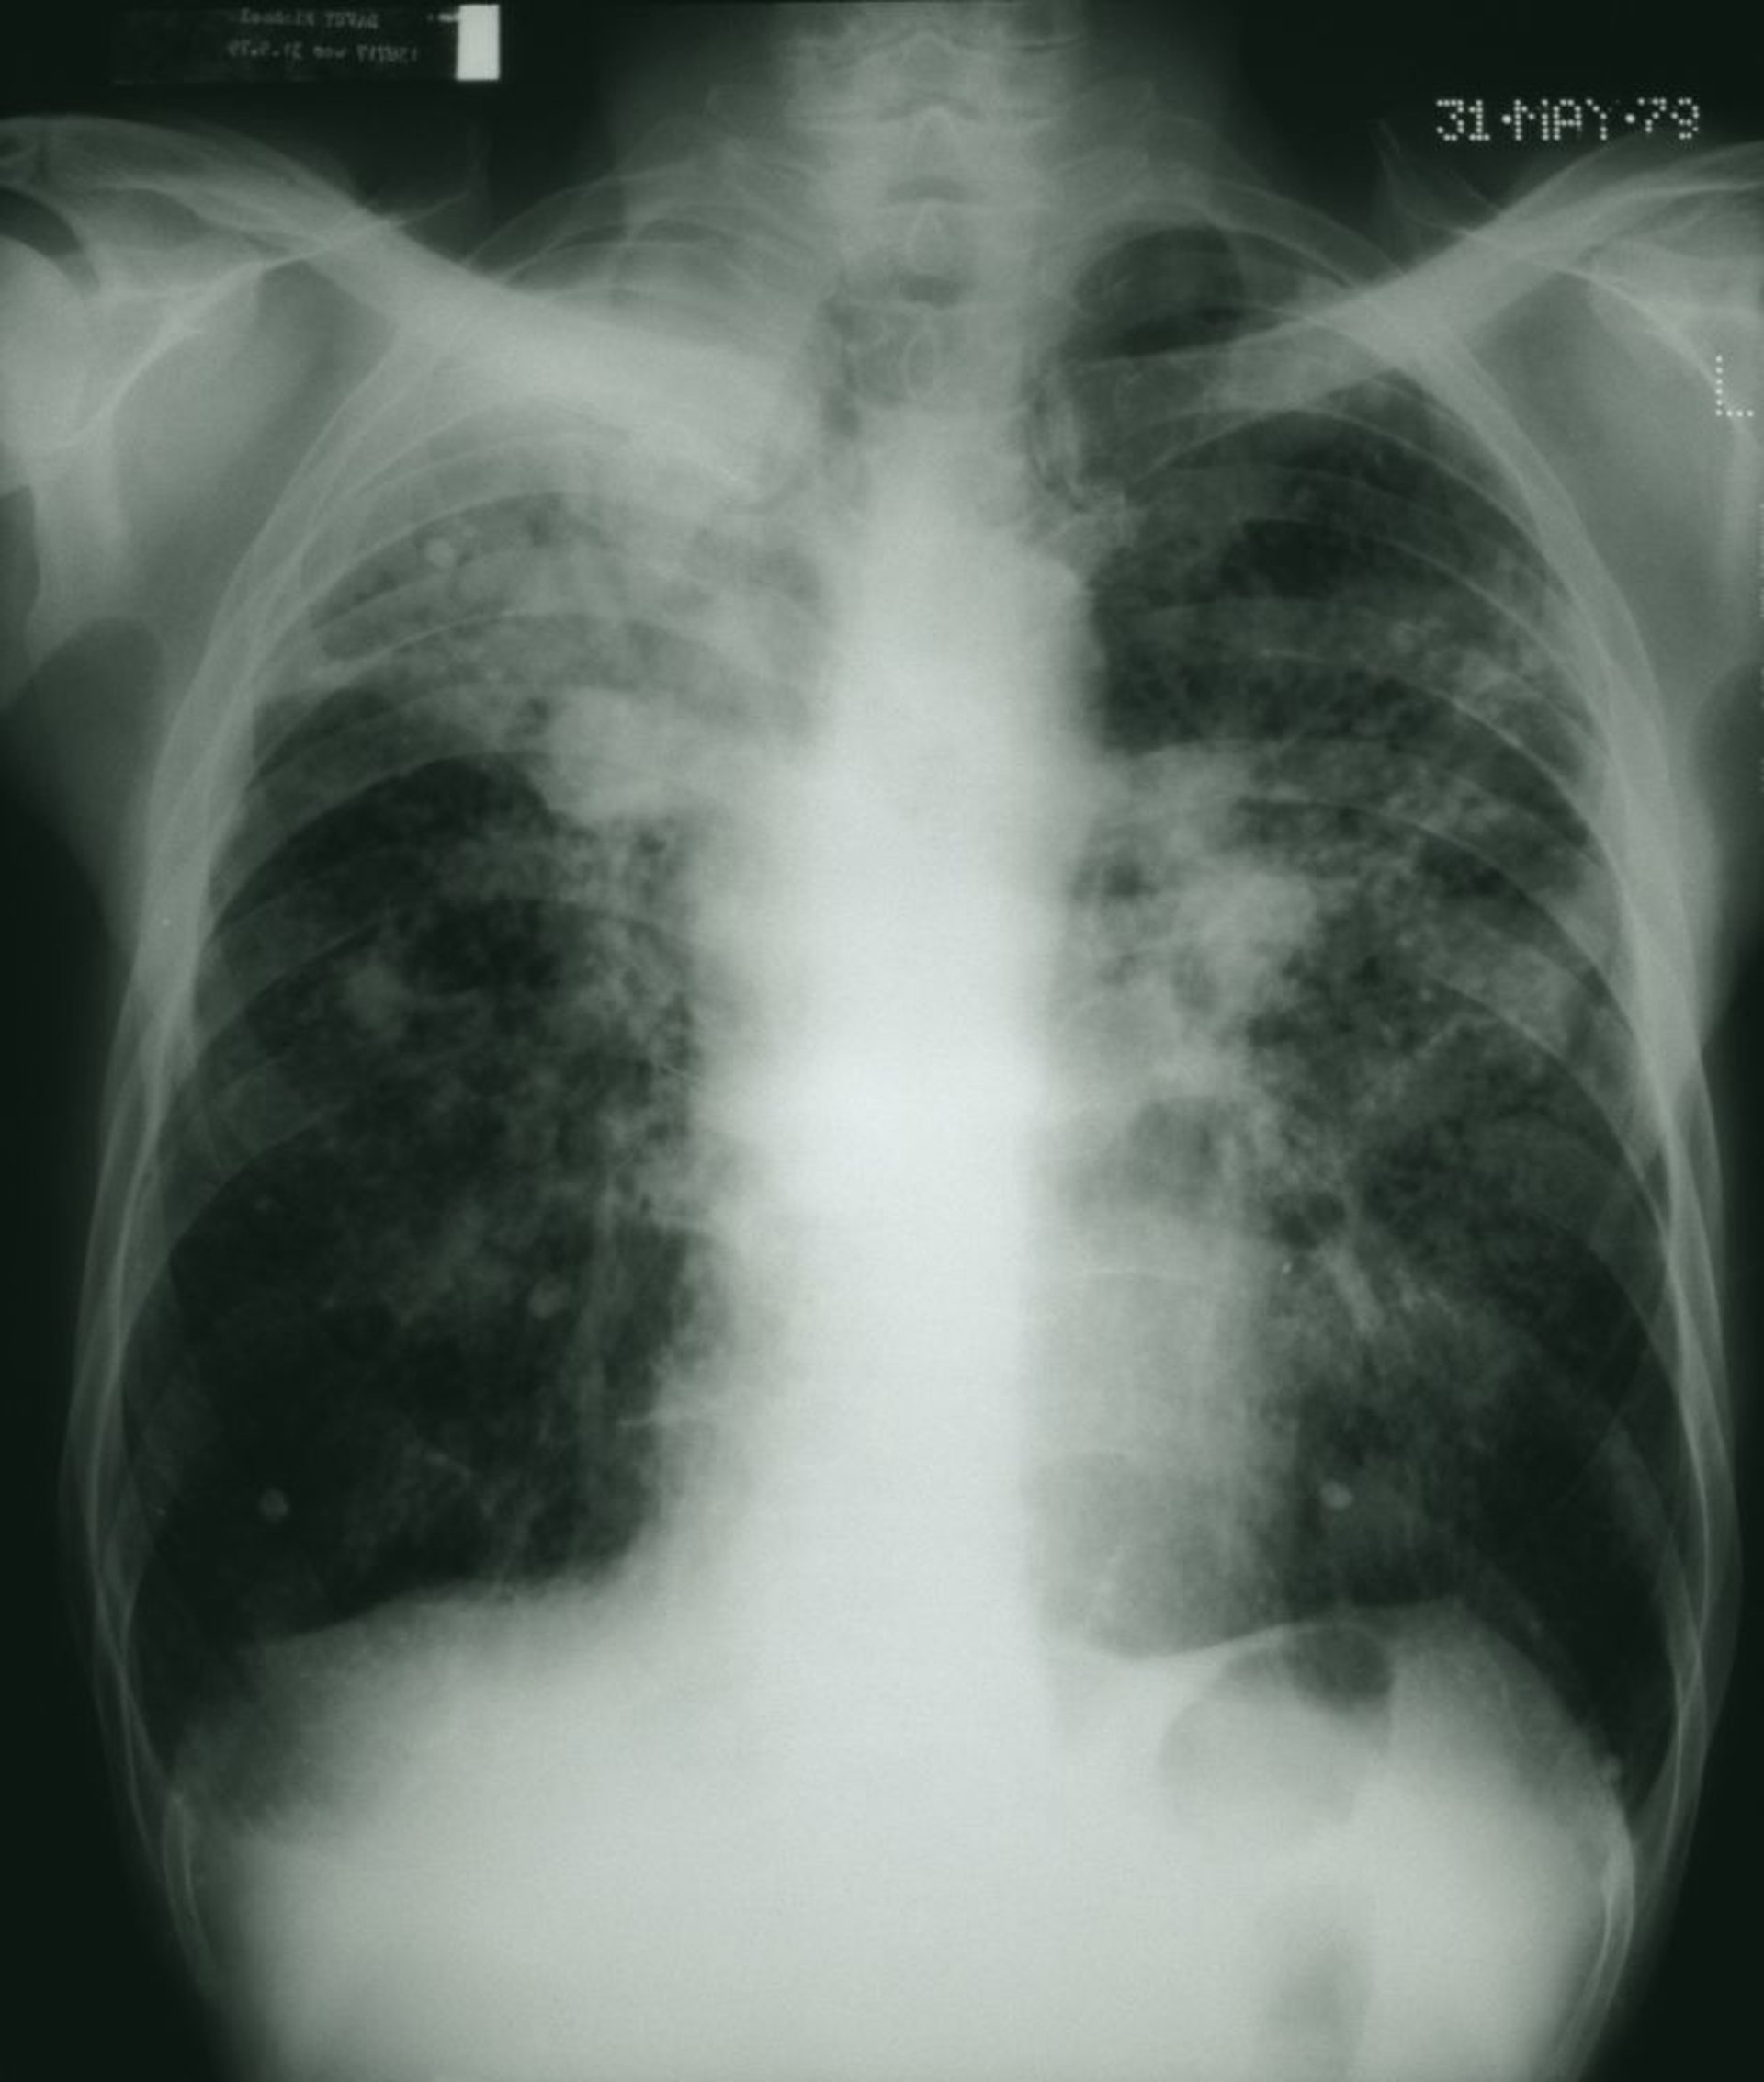

Các trường phổi sẫm màu cho thấy hình dạng lốm đốm với các mảng khối sợi màu trắng phù hợp với bệnh bụi phổi của công nhân than giai đoạn tiến triển.